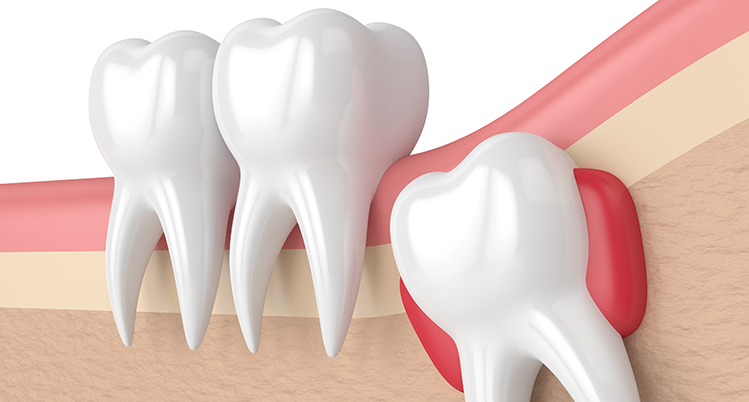

半分頭が出ている親知らずのイラスト

生え方により痛みは変わってきます。歯ぐきを裂きながら生えてくるため歯ぐきから歯の頭が出ようとするときは、歯が出るまでお痛みが続きますが、生えてしまえばお痛みは出ません。横や斜めに生えてくると手前の歯を押すためその痛みが続きます。